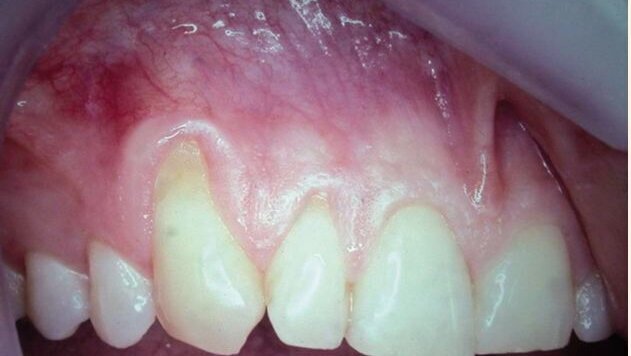

Un patient jeune, adulte, s'est présenté avec une récession bilatérale, au maxillaire supérieur. Le maxillaire supérieur droit supérieur présente une récession étendue sur les dents 12 et 13 (fig. 1). Le maxillaire supérieur gauche supérieur a une récession semblable sur les dents 23 et 23. En plus, la dent 23 a une érosion cervicale, qui a été tachée mais dure et non décalcifiée.

Après anesthésie locale, employant la lidocaïne, la conception désirée du lambeau a été remplie. Il y avait à zone suffisante de GA, actuelle, avant traitement, qui a été préservé et repositionnée coronalement. Sur la réflexion du tissu, une pleine épaisseur de la récession fondamentale était évidente (fig. 2). Le secteur et la récession ont été découverts après le déplacement du débridement et du tissu granulomateux. La membrane résorbable a été formée et placée sur les racines exposées. La membrane a été placée, une première fois sur la dent 13 et la dent a semblé ainsi plus foncée en cela qu'elle ait absorbé le sang. La membrane a été placée, en second lieu, sur la dent 12;

La dent n'avait pas absorbé de sang au moment de la photographie, qui explique la différence de couleur actuelle.